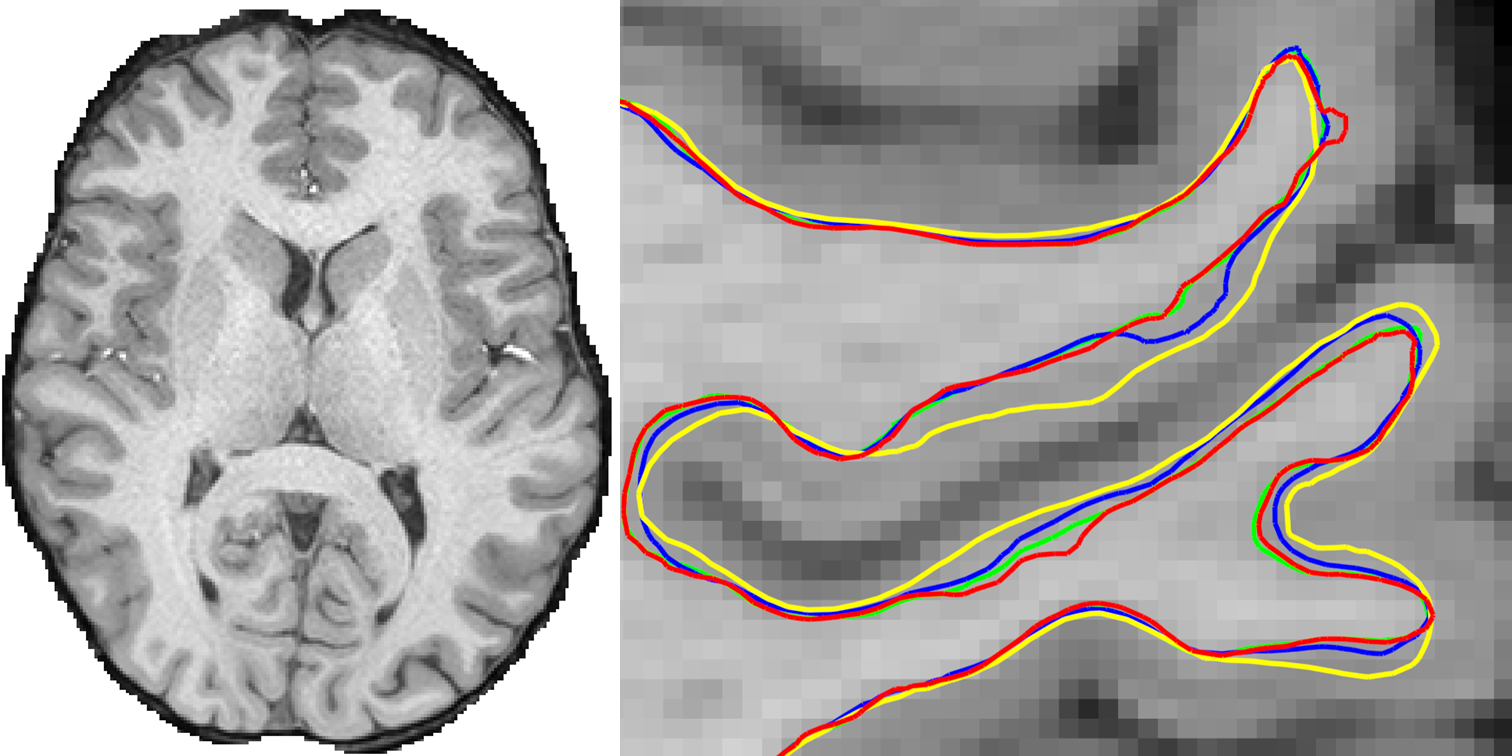

Improved Cortical Surface Reconstruction using Sub-millimeter Resolution MPRAGE by Image Denoising [PDF]

• Tian Q, Zaretskaya N, Fan Q, Ngamsombat C, Bilgic B, Polimeni JR, Huang SY

• NeuroImage, 2021; 233: 117946

Improving In Vivo Human Cerebral Cortical Surface Reconstruction using Data Driven Super-resolution [PDF] [Video1] [Video2]

• Tian Q, Bilgic B, Fan Q, Zaretskaya N, Fultz NE, Ohringer NA, Chaudhari AS, Hu Y, Ngamsombat C, Witzel T, Setsompop K, Polimeni JR, Huang SY

• Cerebral Cortex, 2021; 31: 463-482